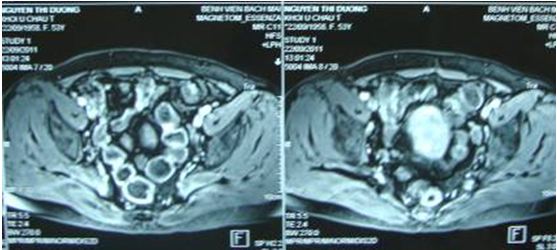

+ Bệnh nhân được tiến hành chụp cộng hưởng từ tiểu khung để đánh giá. Kết quả cộng hưởng từ tiểu khung chụp ngày 22 tháng 9 năm 2011: không có dấu hiệu bất thường

Trước khi quyết định sinh thiết, các chuyên gia chẩn đoán hình ảnh đã xem xét lại và quyết định chụp cộng hưởng từ ổ bụng để đánh giá lại. Bệnh nhân được chụp cộng hưởng từ ngày 6/10/2011. Kết quả: Hình ảnh khối lớn có tính chất dịch ôm quanh rốn thận phải và ôm quanh tĩnh mạch chủ dưới kích thước khoảng 10cm, nghĩ tới u bạch mạch lành tính